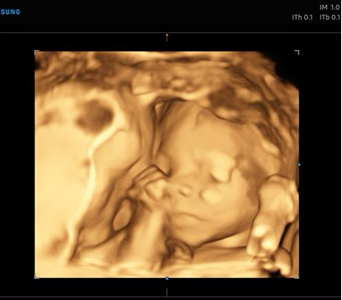

Realizamos revisiones ginecológicas generales, así como control de los embarazos. Asesoramos en el campo de la planificación familiar, la menopausia y también en procesos oncológicos.

Elaboramos diagnósticos precisos gracias a la avanzada tecnología de la que disponemos en nuestro centro, con ecógrafos de alta resolución, colposcopio (para el diagnóstico de patología del cuello del útero) y programa Fénix para la valoración y entrenamiento del suelo pélvico.